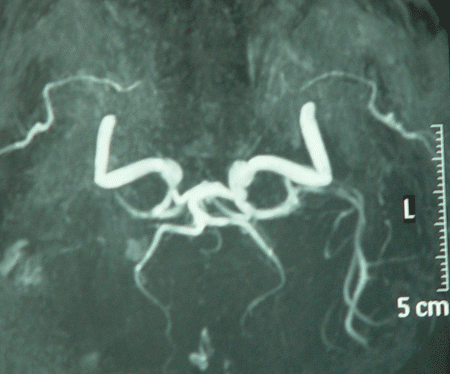

The last picture showing the right MCA eaten by the tumor, despite anatomical preservation during surgery.